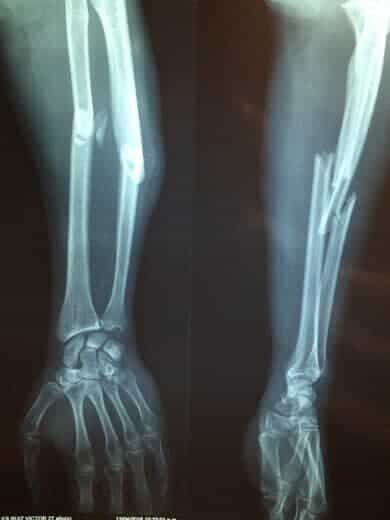

1) Aτελή ανάπτυξη και επιμετάλλωση των οστών οδηγώντας σε οστικές παραμορφώσεις και κατάγματα (πολλαπλά, ξεκινώντας από τη βρεφική ή την παιδική ηλικία, χαμηλής βίας δηλαδή χωρίς σοβαρό τραυματισμό, ανεξήγητα) (εικόνα 1).

2. Ατελής Οστεογένεση

Η ατελής οστεογένεση (ΑΟ) (osteogenesis imperfecta,) περιλαμβάνει μια ετερογενή ομάδα γενετικών διαταραχών που χαρακτηρίζονται από αυξημένη ευθραυστότητα των οστών, χαμηλή οστική μάζα και αυξημένο κίνδυνο οστικών καταγμάτων χαμηλής βίας.

Η ηλικία κατά τη διάγνωση εξαρτάται από τη σοβαρότητα της νόσου. Πέντε κλινικά διακριτές μορφές της νόσου έχουν αναγνωριστεί. Η πιο κοινή και χαρακτηριστική κλινική εκδήλωση όλων των μορφών ΑΟ είναι η ευθραυστότητα των οστών, η οποία εκδηλώνεται ως πολλαπλά αυτόματα κατάγματα.